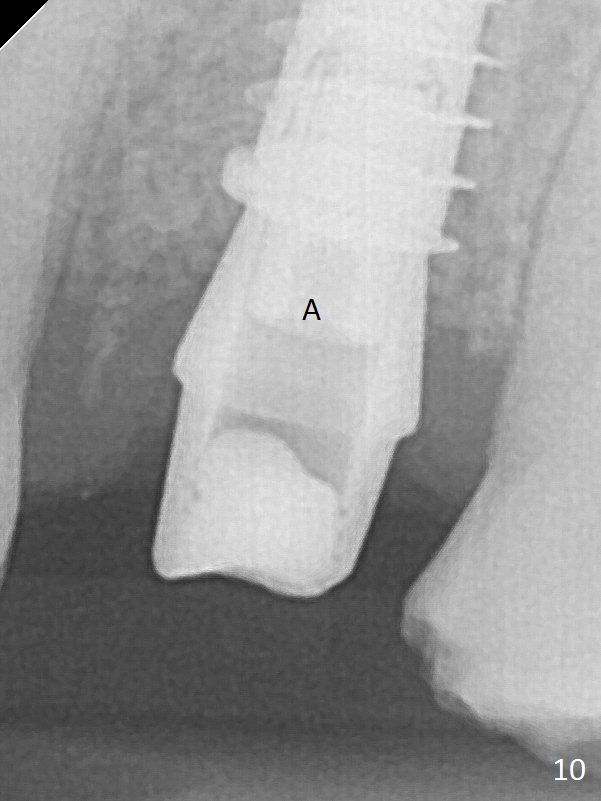

The buccal gingiva over the tooth #13 (Fig.1 white *) with crack (Fig.2 (mesial view of the extracted tooth)) is erythematous with deep buccal (B) pockets, which do not appear to extend the level of exostosis of the neighboring teeth (Fig.1 black *), i.e., coronal to the apical end of the crack with granulation tissue (Fig.2 *). Osteotomy is initiated with a 1.6 mm drill in the palatal aspect of the socket (Fig.3) so that an implant will be placed palatal (Fig.8,11) and there is enough buccal gap for bone graft (Fig.8 *). After withdrawal of 3.3 mm Magic Drill (trephine bur), the osteotomy (Fig.4 O) plug (red outline) is intentionally left in situ. When a 4x11 mm dummy implant is placed (Fig.5 (green outline), 6), the plug is compressed (Fig.5). With placement of a definitive implant (4.5x13 mm, Fig.7 (green), 9), the plug as well as the sinus floor (Fig.4 SF) is lifted (Fig.7 red curved line), 9 (arrowheads)). In brief the autogenous bone is used for sinus lift. There is no intra- or post-op nasal hemorrhage. With a small piece of gauze (Fig.8 G) in the implant well, allograft is placed in the buccal (mainly) and palatal gaps until the level of the implant plateau. Then a 4.5x4(3) mm abutment is placed (Fig.9-10 A). Next another piece of gauze is placed in the space corresponding to the abutment cuff (Fig.11 G) for fabrication of an immediate provisional (Fig.12 P). More bone graft is placed in the soft tissue zone (dual zone technique) after gauze removal and before provisional seating. With dual zone bone graft technique and provisional support, the soft tissue atrophy should be expected to be minimal (Fig.12 *). The zone of exostosis (more coronal) should be much less, since the bone density in the zone is high.